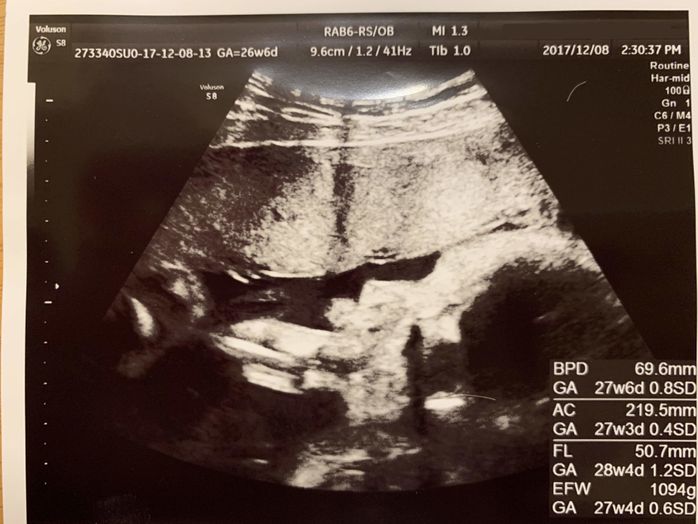

妊娠26週目 2歳長男とこれから生まれてくる赤ちゃん

妊娠26週目の健診。この日は先生から「少し大きめに育っているね」と言われました。上の二人も同じように頭が大きくて会陰切開が必要だったので、「今回も同じかな」と観念しました。その後に、先生の話で女の子とわかり、早速名前を考えるのが楽しみになりました。少し前まで赤ちゃんだった2歳の長男が、「ぼくね、“にいに”になるの」と言ったとき、私はその姿を誇らしく思い、そして愛おしくて、ぽろっと涙が出ました。